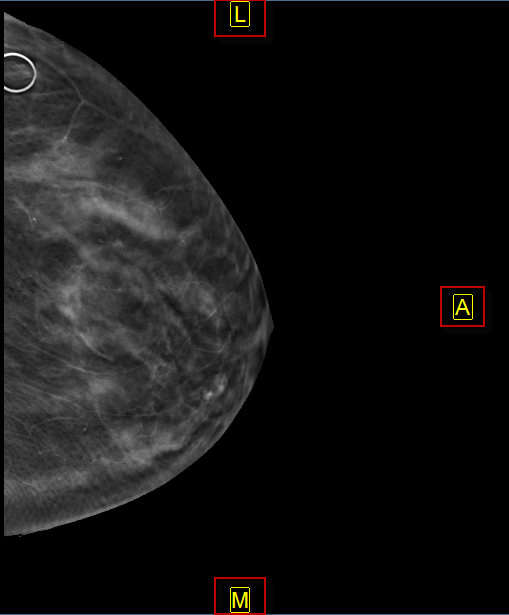

The auto orientation feature overrides the default patient orientation, as defined by the modality, and applies a user-defined orientation. When auto orientation is applied to an image, the patient orientation markers are force to appear on the image and are displayed in yellow.

The images below represent a sinus CT and a Mammography that have Auto-Orientation applied.

2.  P/A sets the posterior (P) or anterior (A) side of sagittal and mammography images to the right edge of the image frame.